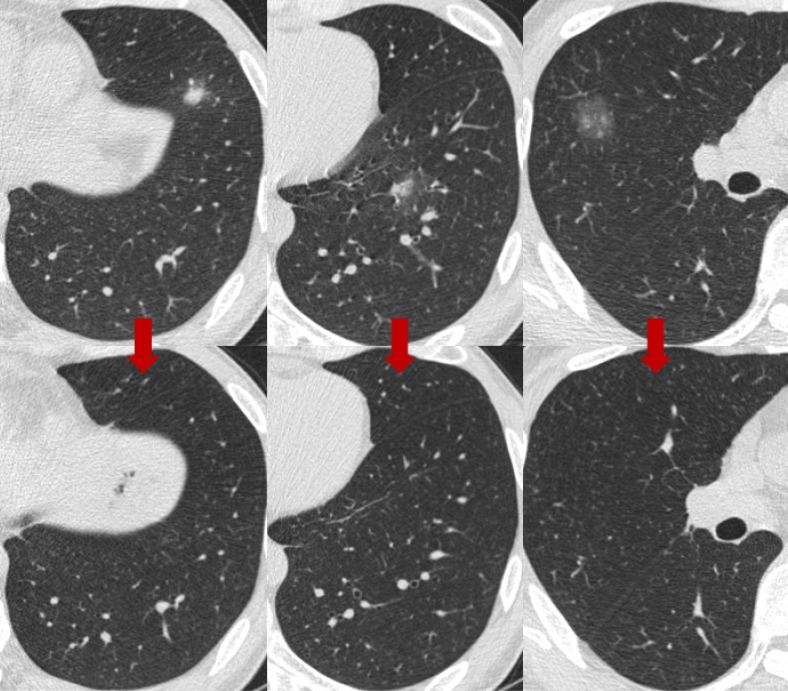

The differential diagnosis of SSNs includes transient inflammatory lesions, focal fibrosis, and premalignant or malignant lesions. Long-term CT surveillance follow-up is needed to manage SSNs that persist for >3 months. Although most SSNs have an indolent clinical course, PSNs may have a more aggressive clinical course than pure GGNs. The proportion of growth and the time to grow is higher and shorter in PSN than pure GGN. In lung adenocarcinoma manifesting as SSNs, mutations were the major driver mutations. Guidelines are available for the management of incidentally detected and screening-detected SSNs. The size, solidity, location, and number of SSNs are important factors in determining the need for surveillance and surgical resection, as well as the interval of follow-up. Positron emission tomography/CT and brain magnetic resonance imaging (MRI) are not recommended for the diagnosis of SSNs, especially for pure GGNs. Periodic CT surveillance and lung-sparing surgery are the main strategies for the management of persistent SSNs. Nonsurgical treatment options for persistent SSNs include stereotactic body radiotherapy (SBRT) and radiofrequency ablation (RFA). For multifocal SSNs, the timing of repeated CT scans and the need for surgical treatment are decided based on the most dominant SSN(s).

SSN的鉴别诊断包括短暂性炎症病变、局灶性纤维化以及癌前或恶性病变。对于持续超过3个月的SSN,需要进行长期CT监测随访。尽管大多数SSN临床病程惰性,但PSN的临床病程可能比纯GGN更具侵袭性。PSN的生长比例和生长时间比纯GGN更高且更短。在表现为SSN的肺腺癌中, 突变是主要驱动突变。对于偶然发现和筛查发现的SSN,有相关管理指南。SSN的大小、实性成分、位置和数量是决定是否需要监测和手术切除以及随访间隔的重要因素。不推荐使用正电子发射断层扫描/CT和脑磁共振成像(MRI)来诊断SSN,尤其是纯GGN。定期CT监测和保留肺组织的手术是管理持续性SSN的主要策略。持续性SSN的非手术治疗选择包括立体定向体部放疗(SBRT)和射频消融(RFA)。对于多灶性SSN,重复CT扫描的时机和手术治疗的必要性取决于最主要的SSN。